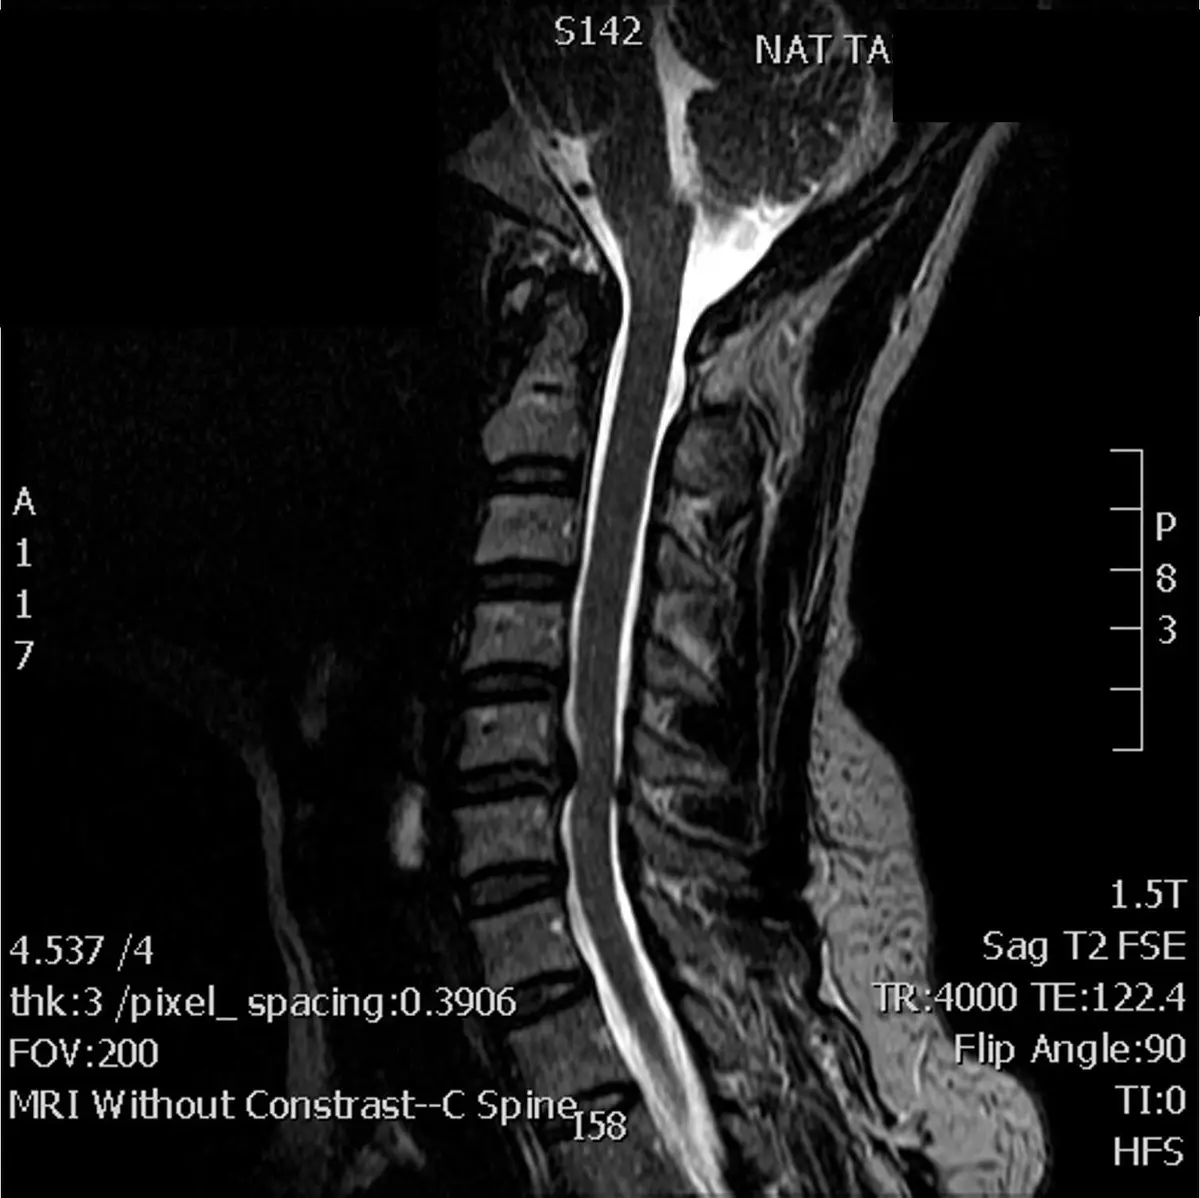

下圖 為一頸痛患者之頸椎核磁共振影像,患者主訴為頸痛、下肢無力以及感覺異常,治療師發現有 Babinski 異常現象,則下列何者 為最可能之問題?

本題圖片為頸椎矢狀面(sagittal)T2 快速自旋回波(T2 Fast Spin Echo, T2 FSE)核磁共振影像,掃描參數為 1.5T、TR 4000、TE 122.4。

- 頸椎排列:頸椎整體曲度可見,生理前凸存在但部分椎間隙有退化性改變

- 脊髓壓迫:在中段頸椎(約 C3-C6 水平)可見多節段椎間盤退化合併骨贅形成(osteophyte),造成硬脊膜囊(thecal sac)前方受壓,脊髓(spinal cord)明顯受到前方壓迫,脊髓前方的腦脊髓液(CSF)亮白訊號空間顯著縮窄

- 脊髓內訊號改變(T2 高訊號):在受壓最明顯的節段,脊髓實質內可見 T2 訊號增強(T2 hyperintensity),提示脊髓水腫(edema)、膠質增生(gliosis)或脊髓軟化(myelomalacia),是脊髓已受到慢性損傷的影像